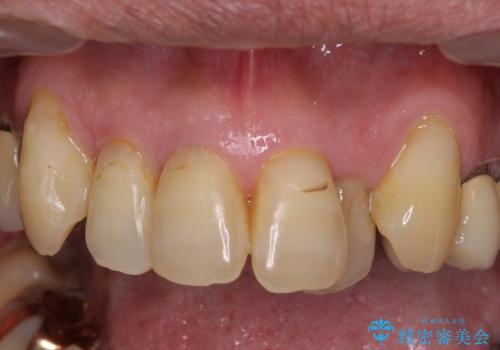

初診来院時には矯正治療を行うことは想像していなかったようで、治療後には咬みやすさだけでなく、前歯が大変審美的に仕上がり、患者様には大変満足していただきました。

- 天然歯を削ります

- 硬い素材は天然歯を傷つけてしまう場合があります

- かみ合わせや歯ぎしりが強すぎる方はセラミックが割れてしまう可能性があります